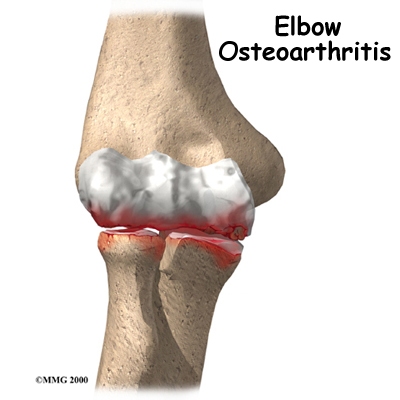

Sustaining an elbow injury, however, can lead to problems with the joint later in life. This is true for any injury to a joint but the elbow is one of the joints particularly sensitive to developing problems later on. The initial injury can change the way the joint works just enough to cause extra wear and tear to the surfaces of the joint. Over time, the joint degenerates, causing pain and difficulty with daily activities. This condition is called osteoarthritis (OA), degenerative arthritis, or posttraumatic arthritis.

OA is caused by degeneration of the articular cartilage of a joint. Degeneration is wear that happens over time. Doctors use the term degenerative arthritis to describe the wear and tear of a joint over many years. Degenerative arthritis is another term for OA. Some doctors use the term degenerative arthrosis. Arthrosis means that the joint is wearing out.

OA is caused by degeneration of the articular cartilage of a joint. Degeneration is wear that happens over time. Doctors use the term degenerative arthritis to describe the wear and tear of a joint over many years. Degenerative arthritis is another term for OA. Some doctors use the term degenerative arthrosis. Arthrosis means that the joint is wearing out.

A bad sprain or fracture can damage the articular cartilage. The cartilage can also be bruised when too much pressure is put on the cartilage surface. In some cases OA may be idiopathic which means there isn’t a known reason for the condition, but most of the time, elbow OA is linked with excess use of the arm or a previous injury.

At the time of injury the cartilage surface may not look any different if it has not been directly injured. The injury to the cartilage often doesn't show up until months later. In some cases, however, the damage to the cartilage with the initial injury is severe. Pieces of the cartilage can actually be ripped away from the bone and these pieces do not grow back. Usually they must be surgically removed otherwise they cause problems with the functioning of the joint. If the pieces aren't removed, they may float around in the joint, causing it to catch. These pieces are referred to as loose bodies or joint mice. In addition to catching in the joint they can also cause a lot of pain and do more damage to the joint surfaces if left inside the joint.

Unfortunately the human body does not do a good job of repairing these holes in the cartilage surface of joints. The holes fill up with scar tissue. Scar tissue is not as slick or rubbery as the articular cartilage so the joint mechanics suffer.

Unfortunately the human body does not do a good job of repairing these holes in the cartilage surface of joints. The holes fill up with scar tissue. Scar tissue is not as slick or rubbery as the articular cartilage so the joint mechanics suffer.

An injury doesn't have to directly damage the articular cartilage to start the process of OA. Any injury to the elbow joint can change the way the joint works which then starts the cycle of wear and tear on the joint. For example, after an elbow fracture the bone fragments may not line up exactly. If this is the case they then heal in a slightly different position from prior to the injury, which may only mildly modify how the joint works, but is enough to change the wear and tear on the cartilage.

A dislocation can also cause lasting damage to the elbow joint. After the ligaments have been injured in a dislocation, the elbow joint may move differently. This change in movement alters the forces on the articular cartilage. Similar to how a machine works, if one mechanism is out of balance, there can be more friction between the moving parts and it wears out faster.

Over many years, this imbalance in joint mechanics can damage the articular cartilage. Since articular cartilage cannot repair itself very well, the damage adds up. Finally, the joint can no longer compensate for the damage, and the elbow begins to hurt.

OA of the elbow is a similar process to that which occurs in the hip or knee, however, more often in the elbow, the articular cartilage itself isn’t damaged with an initial injury, whereas in the hip or knee it often is. In the elbow the biggest changes occurring after an injury are hypertrophic osteophyte (bone spur) formation and capsular contracture.

Capsular contracture refers to the process by which the capsule dries out and tightens up. The capsule has two layers: a fibrous covering that surrounds the joint and an inner lining. The inner layer is called the synovium. The synovial layer holds the lubricating fluid inside the joint. If this fluid dries up, or the joint capsule contracts, the mechanics of the elbow joint change, and this in turn applies more pressure to the articular cartilage and wears it out quicker.